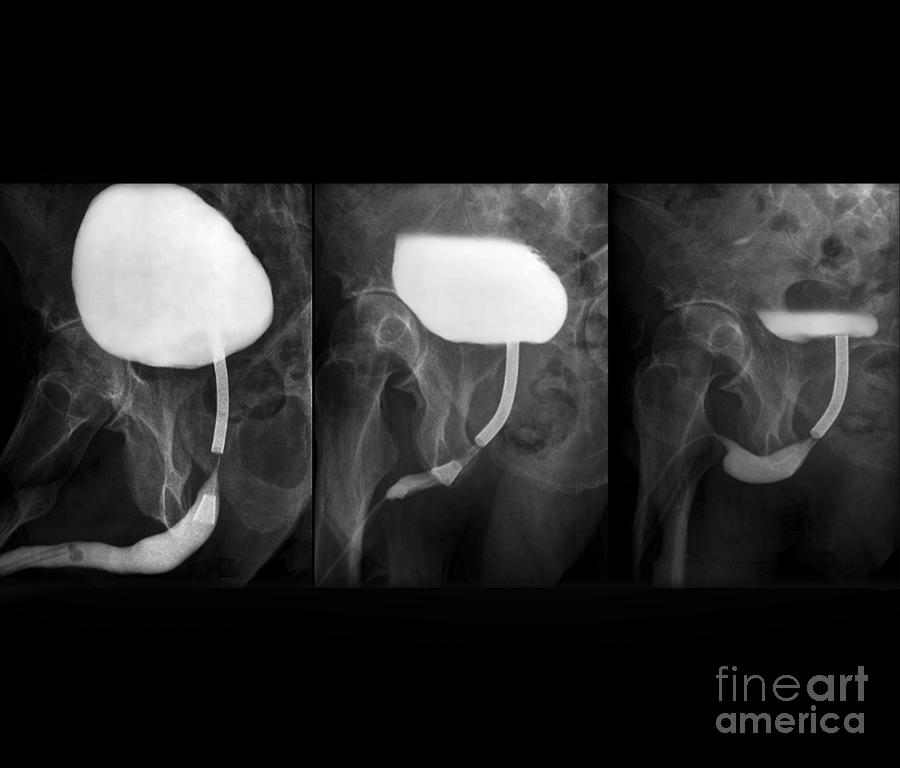

Основными методами верификации стриктуры уретры является

Основными методами верификации стриктуры уретры является 111 фотографий